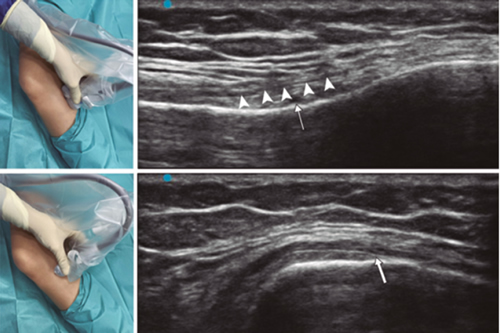

Ultrasound-guided genicular nerve radiofrequency

Fig. 3. Sonoanatomy and technique for performing superior medial genicular nerve block (SMGN). The transducer is located on the distal long axis of the femur and once the position of the SMGN (asterisks) is known, the probe is rotated 90 degrees to obtain a view of the femur short-axis (don't forget to keep the same depth that we find the SMGN on the long axis). VM (vastus medialis).

In order to achieve a correct location of anatomical landmarks by ultrasound we must place the patient in supine position with the knee flexed and a pillow under the popliteal fossa (14,16,19).

Fig. 4. Sonoanatomy and technique for performing inferior medial genicular nerve block (IMGN). The transducer is located on the proximal long axis of the tibia and we identify the vasculonervious package of the IMGN (arrow) just below medial collateral ligament (arrowheads). Then the probe is rotated 90 degrees to obtain a short-axis view of the tibia (don't forget to keep the same depth as the IMGN found on the long axis).

After performing knee asepsis/antisepsis, surgical field placement, and the sterile sheath of the high frequency linear transducer, we proceed to locate the SMGN (Figure 3). Placing the probe in a coronal plane on the inner face of the knee, we slide it cranially to visualize the junction of the metaphysis to the femoral diaphysis and the superior medial genicular artery/nerve (ASMGN), usually located near the periostium of the femur (if this neurovascular structure is not found, the junction between metaphysis and femoral diaphysis is taken as a reference). The mid-point of the transducer corresponding to ASMGN is then marked on the skin and the transducer is rotated to be placed in the transverse or axial plane to view ASMGN on the short axis (if this structure is not visible, confirm that we are at 50 % depth of the femur). In this cross-section the needle of the TRF is advanced in plane from anterior to posterior toward the ASMGN or to a depth of 50 % of the thickness of the femur. Finally, the transducer is rotated 90° again, leaving it in a coronal plane to check that the needle tip is near the ASMGN or the junction of the metaphysis and femoral diaphysis (14,16,19).

To locate the IMGN (Figure 4), we placed the transducer in a coronal plane on the inner face of the knee, sliding it caudally to identify the diaphysis junction with the tibial metaphysis and the inferomedial genicular artery/nerve (AIMGN). And we repeat the same steps we used for SMGN. If the AIMGN is not found, the reference to be taken shall be the depth of 50 % of the thickness of the tibia (14,16,19).